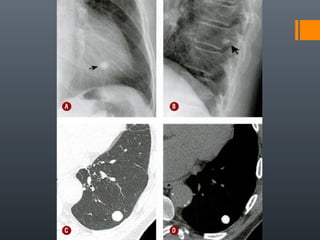

O documento discute vários conceitos radiológicos incluindo consolidação, atelectasia, nódulos, pseudocavidades e padrões intersticiais, fornecendo definições, sinais e diagnósticos diferenciais para cada tópico. Ele também discute a redução da atenuação pulmonar e fornece um link para mais informações.